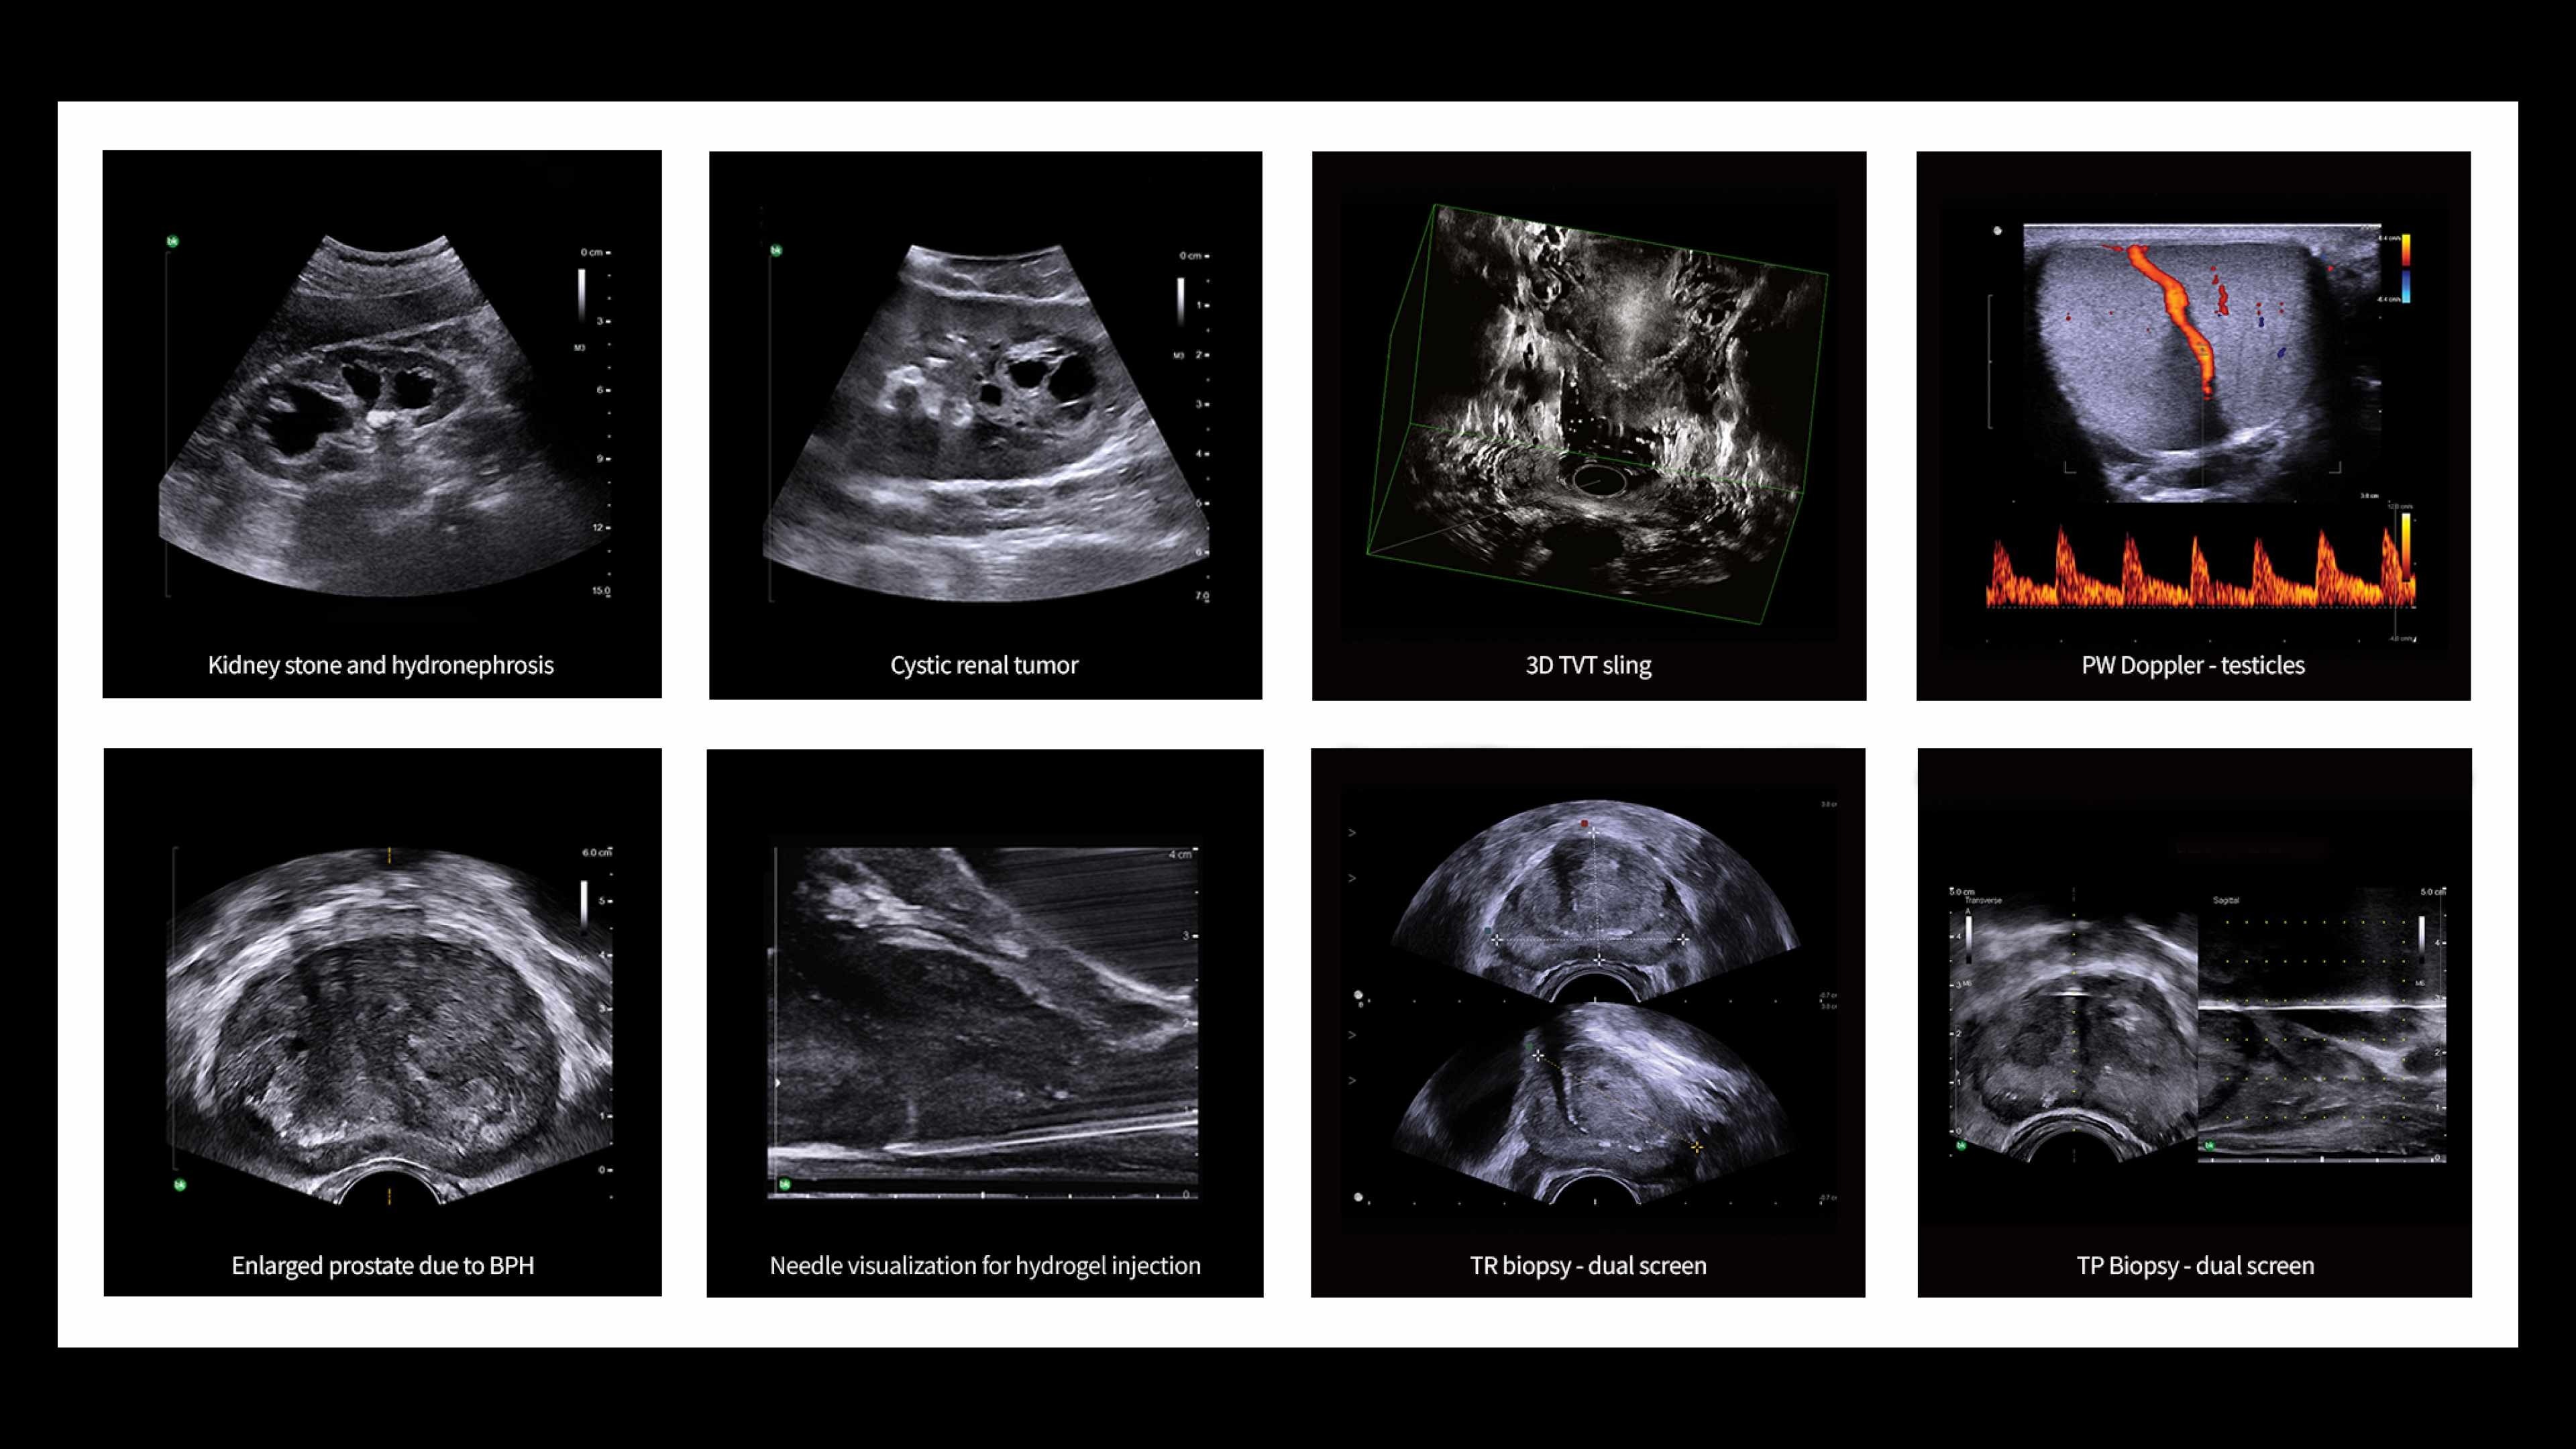

The bkPortfolio includes a family of bkActiv ultrasound systems. The bkActiv S series for urology is an advanced, high-resolution ultrasound system designed for imaging and interventional guidance.

The bkActiv S series for urology is an advanced, high-resolution ultrasound system designed for imaging and interventional guidance. This is the latest innovation in the bkActiv family of Active Imaging Systems within the bkPortfolio.

Designed to elevate the user experience in urological and colorectal and pelvic floor procedures, the bkActiv S series continued the bridge building between the clinic and the OR.

Comprehensive range of sterilizable, specialty transducers

Advanced transducer technology and a comprehensive selection of styles and sizes offer superb access across a wide range of body types.